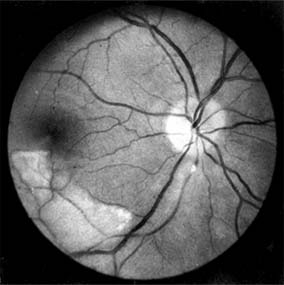

This is extremely rare, though certain clinical appearances have been attributed to ciliary vessel occlusion. These include small pale areas in the equatorial region that resolve to leave mottled pigmentary areas (Elschnig's spots) due to necrosis of the pigment epithelium. Larger infarcts may occur and may be triangular or linear (Figure 15-3).

Figure 15-3

Figure 15-3: Anti-phospholipid antibody syndrome. Fluorescein angiogram demonstrates choroidal infarcts in a patient who presented with multiple strokes.